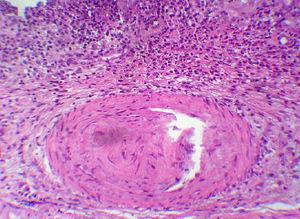

Figura 2. Imagen del corte transversal de la biopsia del cartílago auricular.

Figura 3. Detalle de la biopsia de cartílago auricular: pérdida de la tinción basofílica de la matriz cartilaginosa, con infiltrado de polimorfonucleares y monocitos alrededor del tejido vascular. Algún condrocito con necrosis central sustituido por tejido fibroso.